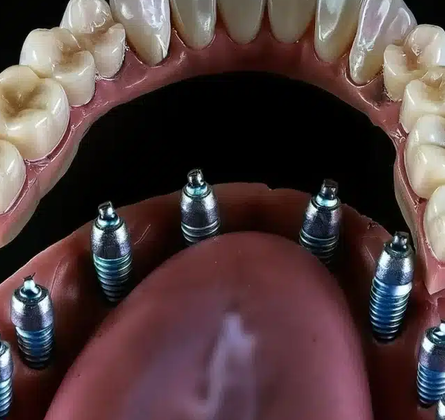

Los implantes dentales son estructuras de titanio o zirconio que reemplazan la raíz de un diente perdido, sobre las cuales se coloca una corona o prótesis que imita el diente natural tanto en forma como en función. Constituyen hoy en día la alternativa más avanzada y duradera para restaurar piezas dentales ausentes, ya que se integran al hueso mediante un proceso biológico llamado osteointegración, proporcionando una base sólida y permanente.

El tratamiento comienza con una evaluación clínica y radiográfica para determinar la cantidad y calidad del hueso disponible. Si el paciente es apto, se procede a la colocación quirúrgica del implante, seguida de un período de cicatrización que puede durar de tres a seis meses, durante el cual el implante se fusiona con el hueso. Posteriormente se instala un pilar que servirá de soporte a la corona definitiva. En algunos casos, dependiendo de la estabilidad del implante y las condiciones óseas, es posible colocar una corona provisional el mismo día de la cirugía, lo que se conoce como carga inmediata.

Los avances tecnológicos han permitido que la implantología evolucione notablemente. Hoy se utilizan sistemas guiados por computadora para colocar los implantes con mayor precisión, materiales cerámicos para una mejor estética y superficies nanotratadas que aceleran la integración ósea. Si bien la inversión inicial es mayor que la de otras alternativas, su durabilidad, estabilidad y naturalidad los convierten en una solución a largo plazo.